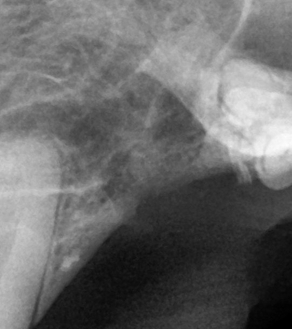

덴탈 X-ray를 통해 치아 내부 상태를 정확히 파악한 후, 아이에게 불필요한 고통 없이 최선의 결정을 내릴 수 있도록 안내합니다.

BEFORE

AFTER